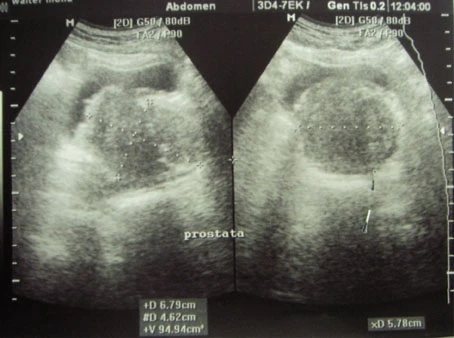

ultrassonografia de próstata

A ultrassonografia de próstata é um exame não invasivo que utiliza ondas sonoras de alta frequência para produzir imagens da próstata. É um exame importante para detectar alterações na próstata, como o aumento de tamanho, nódulos ou tumores. O exame é realizado com o paciente deitado de barriga para baixo e um gel é aplicado na região do abdômen. O médico urologista utiliza um aparelho de ultrassom para visualizar a próstata e avaliar sua estrutura. O exame é rápido e indolor, e não requer preparação especial. É recomendado para homens a partir dos 50 anos ou mais cedo em casos de histórico familiar de câncer de próstata. A DK Urologistas oferece esse exame com equipamentos modernos e profissionais especializados para garantir a precisão do diagnóstico. Agende sua consulta e cuide da sua saúde!